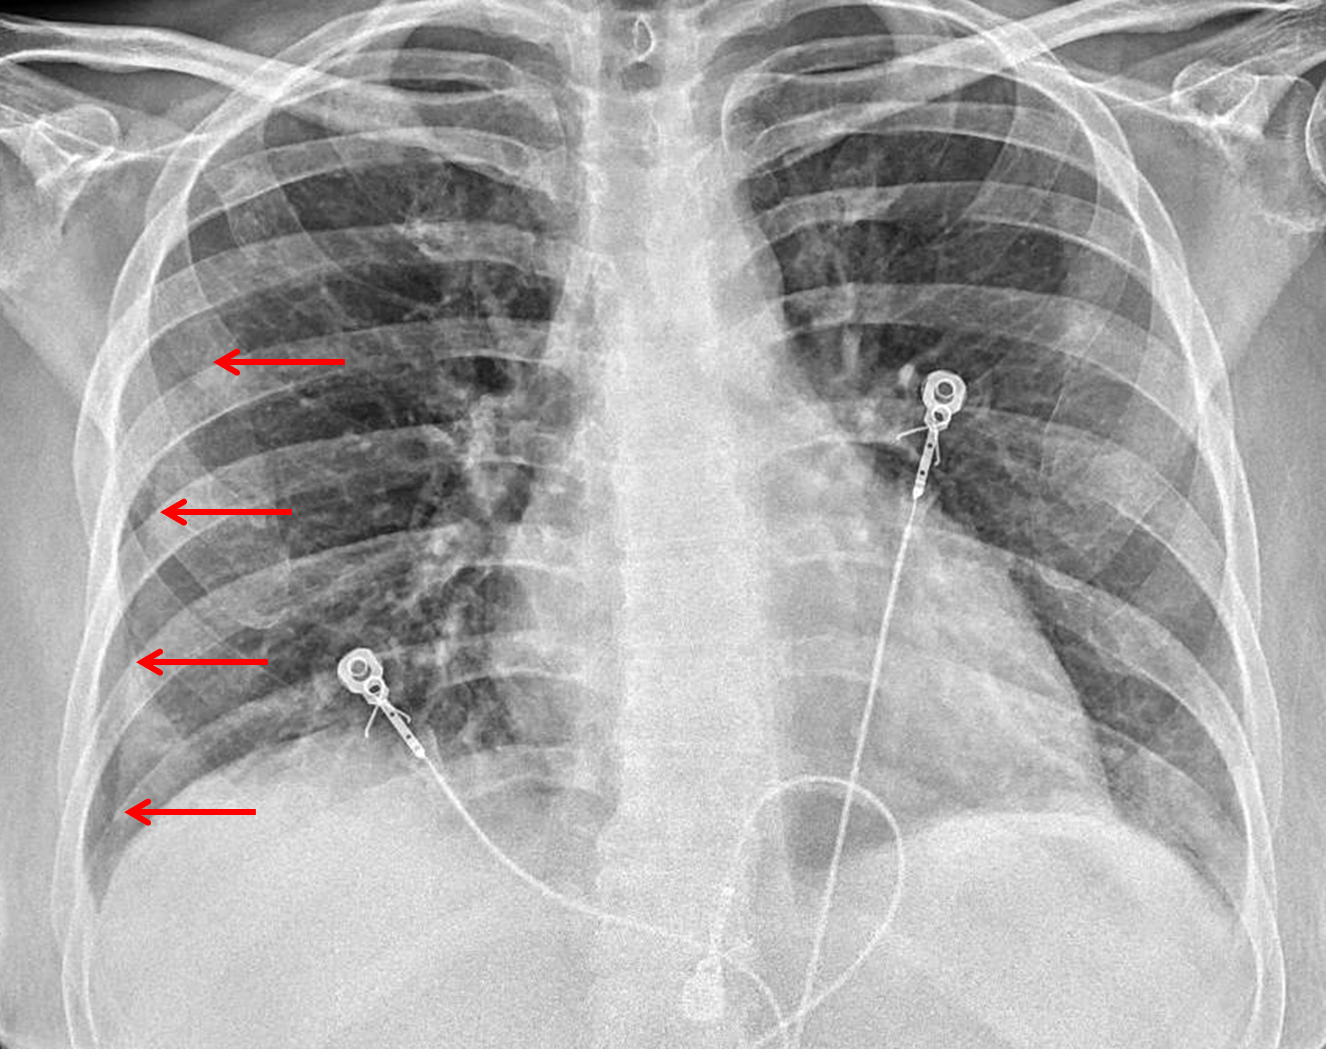

Age: 35

Sex: Female

Indication: Cough, fever

Sample ReportMild bibasilar patchy opacities which may represent atelectasis, aspiration, or pneumonia. Consider dedicated PA and lateral chest radiographs for further evaluation.

Vertically-oriented line traversing the lateral right lung field likely represents a skin fold. Repeat imaging could be considered if there is high clinical concern for pneumothorax.